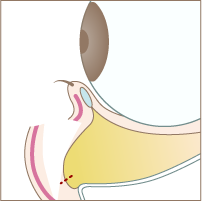

Treatment Step施術手順

Step 01

まぶたの裏側の赤い点線部分を切開します

Step 02

脂肪が溜まっている部分の下側の隔膜を切開します。

Step 03

隔膜と眼窩脂肪を一塊として引き下げ、骨膜に縫合します。

Step 04

切開した部分を縫合して完成です。